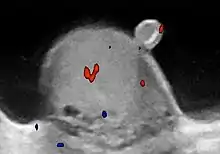

Patients with testicular lymphoma are usually old aged around 60 years of age, present with painless testicular enlargement and less commonly with other systemic symptoms such as weight loss, anorexia, fever and weakness. Bilateral testicle involvements are common and occur in 8.5% to 18% of cases. At sonography, most lymphomas are homogeneous and diffusely replace the testis [Fig. 7]. However focal hypoechoic lesions can occur, hemorrhage and necrosis are rare. At times, the sonographic appearance of lymphoma is indistinguishable from that of the germ cell tumors [Fig. 8], then the patient's age at presentation, symptoms, and medical history, as well as multiplicity and bilaterality of the lesions, are all important factors in making the appropriate diagnosis.

Doppler ultrasound of epididymitis, seen as a substantial increase in blood flow in the left epididymis (top image), while it is normal in the right (bottom image). The thickness of the epididymis (between yellow crosses) is only slightly increased (7 mm).

Doppler ultrasound of epididymitis, seen as a substantial increase in blood flow in the left epididymis (top image), while it is normal in the right (bottom image). The thickness of the epididymis (between yellow crosses) is only slightly increased (7 mm). Doppler ultrasound of the scrotum of the same case, in the axial plane, showing orchitis (as part of epididymo-orchitis) as hypoechogenic and slightly heterogenic left testicular tissue (right in image), with an increased blood flow. There is also swelling of peritesticular tissue.

Doppler ultrasound of the scrotum of the same case, in the axial plane, showing orchitis (as part of epididymo-orchitis) as hypoechogenic and slightly heterogenic left testicular tissue (right in image), with an increased blood flow. There is also swelling of peritesticular tissue.